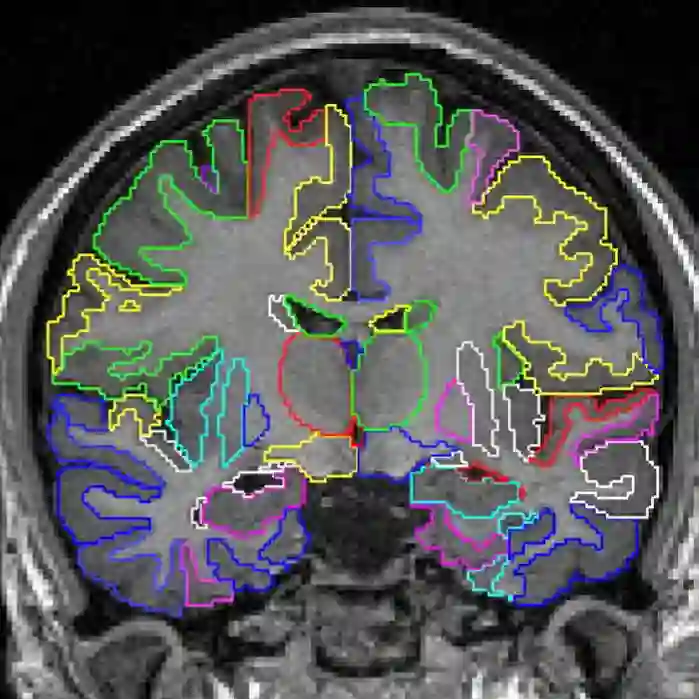

3、Data augmentation using learned transformations for one-shot medical image segmentation(利用学习变换进行数据增强,实现one-shot医学图像分割)

作者Amy Zhao, Guha Balakrishnan, Frédo Durand, John V. Guttag, Adrian V. Dalca

摘要图像分割是医学应用中的一个重要课题。基于卷积神经网络的方法获得了最先进的精度;然而,它们通常依赖于带有大型标记数据集的监督训练。医学图像的标注需要大量的专业知识和时间,而典型的手工调优的数据增强方法无法捕捉这些图像中的复杂变化。我们提出了一种自动数据增强方法来合成标记医学图像。我们在分割磁共振成像(MRI)脑扫描的任务中展示了我们的方法。我们的方法只需要一次分段扫描,并利用半监督方法中的其他未标记扫描。我们从图像中学习转换模型,并使用该模型和带标记的示例来合成其他带标记的示例。每个转换都由空间变形场和强度变化组成,从而能够综合复杂的效果,如解剖学和图像采集过程的变化。我们展示了使用这些新示例训练有监督的分割器,对于one-shot生物医学图像分割的最先进方法有着显着的改进。我们的代码可以在https://github.com/xamyzhao/brainstorm上找到。